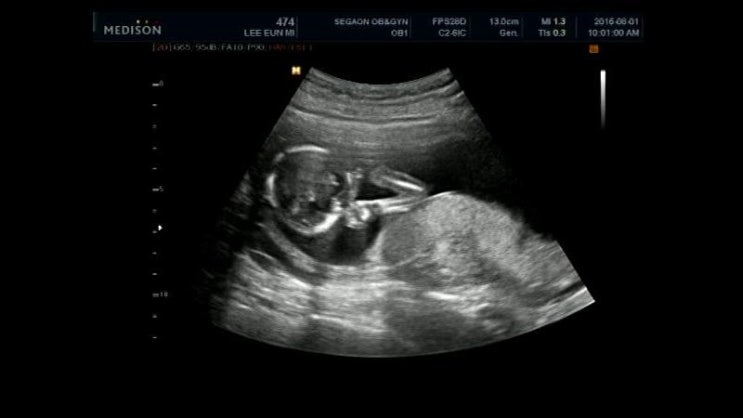

2016년 8월 1일 오복이 15주 3일차

이제 임신중기라서 4주에 한번 오복이 만나게 되었어요~ 잘크는지 걱정이되는데 4주가 빠른...